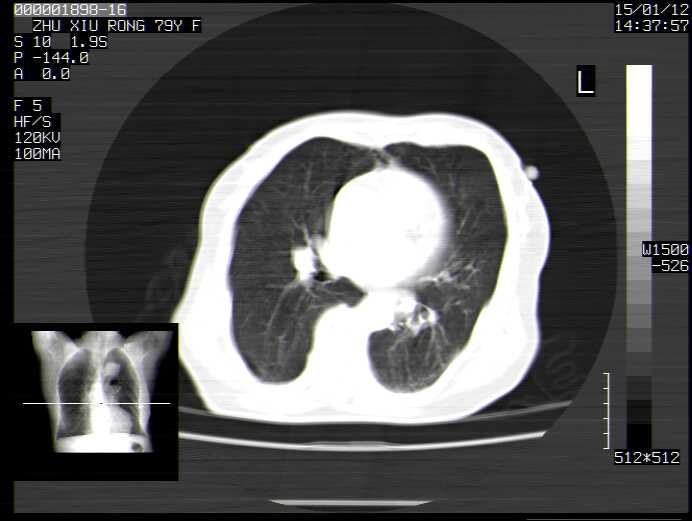

CT49741:请会诊 女 79岁

右胸痛 一周。

慢性支气管炎合并左下肺炎症。肺气肿。

慢支、肺气肿,左下肺炎症。

慢性支气管炎,肺气肿,支扩带排。